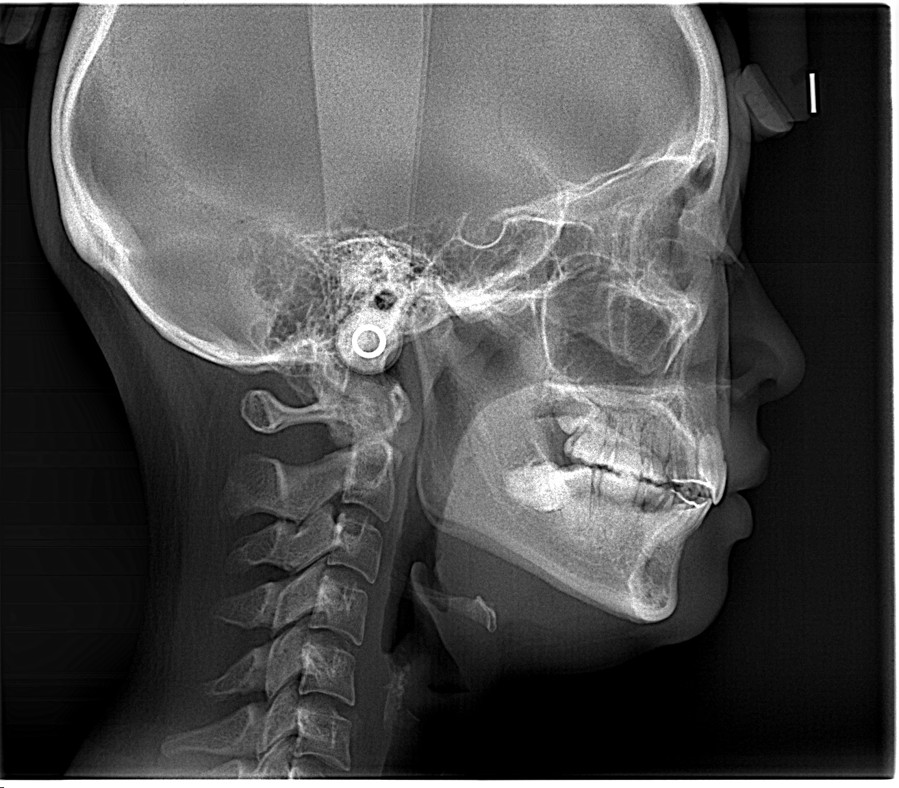

After

この角度が深くなる(120〜130度に近づく)ことで、唇がスッと中に入り、横顔のEラインが整います。数字で見ると、矯正でどれだけ歯の土台から角度が変わったかが一目瞭然です。

前歯の角度を整えるだけで、横顔は「整形級」に変わります。

今回の症例は、角度99°から理想の130°へ。